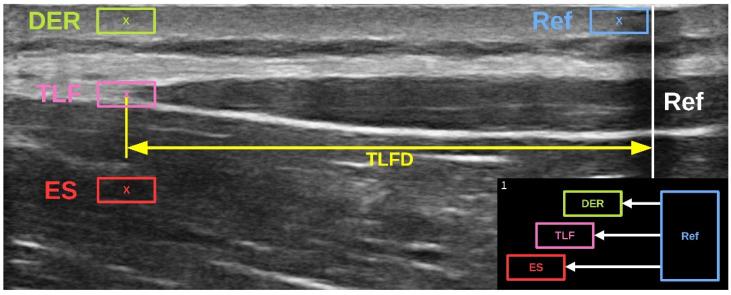

A new method for quantifying thoracolumbar fascia deformation (TLFD) and its shear capacity has been introduced, and its reliability for discriminating patients with low back pain (LBP) from healthy controls has been demonstrated in a recent paper. The aim of this study was to investigate the method in terms of criterion validity. First, the concurrent validity of the TLFD ultrasound measurement method (TLFD_US) was tested in vitro, using a custom-made tissue sliding device that mimics tissue shearing and generates ground truth data. Second, ultrasound images and videos of TLFD were acquired from 10 acute LBP patients and 10 healthy controls by a blinded assessor. In vivo, the concurrent validity of TLFD_US and speckle tracking analysis was then tested. Third, the contribution of the surrounding tissue layers of the erector spinae muscle and dermis to TLFD was calculated using multiple linear regression. The in vitro concurrent validity between TLFD_US and ground truth was excellent (ICC = 0.99; < 0.001). In vivo, the concurrent validity between TLFD_US and speckle tracking analysis was large (r = 0.701; < 0.001). Multiple linear regression revealed a large effect regarding the relationship between dermis shear and TLFD (R = 0.353; = 0.01). TLFD_US showed excellent criterion validity. Its suitability for capturing morphological parameters of the thoracolumbar fascia is further reinforced.

一种用于量化胸腰筋膜变形(TLFD)及其剪切能力的新方法已被提出,并且其在区分腰痛(LBP)患者与健康对照方面的可靠性已在最近的一篇论文中得到证实。本研究的目的是从标准效度方面对该方法进行研究。首先,使用定制的组织滑动装置在体外测试TLFD超声测量方法(TLFD_US)的同时效度,该装置模拟组织剪切并生成真实数据。其次,由一名不知情的评估者从10名急性LBP患者和10名健康对照中获取TLFD的超声图像和视频。然后在体内测试TLFD_US与散斑追踪分析的同时效度。第三,使用多元线性回归计算竖脊肌和真皮周围组织层对TLFD的贡献。TLFD_US与真实数据之间的体外同时效度极佳(ICC = 0.99;<0.001)。在体内,TLFD_US与散斑追踪分析之间的同时效度较大(r = 0.701;<0.001)。多元线性回归显示真皮剪切与TLFD之间的关系具有较大影响(R = 0.353;= 0.01)。TLFD_US显示出优异的标准效度。其在捕获胸腰筋膜形态学参数方面的适用性得到了进一步加强。